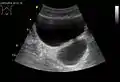

Bladder diverticula containing stones: the bladder wall is thickened due to possible transitional cell carcinoma.- Bladder diverticula as seen on ultrasound with doppler[18]

- Bladder diverticula as seen on ultrasound[18]